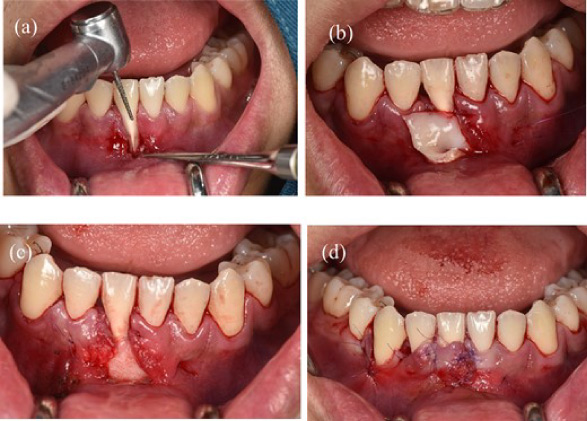

Before surgery: scaled the lower incisors and endodontic treatment. After 2 weeks, the inflammation of the gingival had decreased and we can start the gingival graft treatment and the surgical procedure is depicted below (Fig. 3). Local anesthesia then followed by meticulous preparation of the tooth surface using a high-speed handpiece. To prepare the root surface, a 24% ethylenediaminetetraacetic acid (EDTA) gel was used. To obtain an epithelialized connective tissue graft (CTG), tissue was harvested from the hard palate in the area from first premolar to first molar. The graft was carefully shaped and sized based on the specific measurements of the gingival recession defect. A specialized 15C blade was utilized for this precise procedure. Subsequently, a thin layer of epithelial tissue, ~0.5–1 mm in thickness, was eliminated from the graft using a high-speed handpiece and 2 mm round diamond bur, except for the specified epithelial section as illustrated in (Fig. 2a). A piece of connective tissue in size 13 × 13 × 1.5 mm was harvested to adequately cover the entire tooth root (Fig. 2b and c). Afterward, Emdogain was applied to the complete root surface, starting from the most apical bone level to maximize the therapeutic potential of Emdogain in facilitating tissue regeneration and promoting periodontal healing. On the right side, where gingival recession was observed on the teeth, a flap with varying thickness was raised. This flap featured a split-thickness technique in the papillae and vestibular sulcus, while maintaining full thickness at the center. An incision was created to alleviate tension, specifically at a location distant to the right canine. Through the sulcular access on the left side of tooth 41, the graft was inserted into the tunnel, and the epithelial segment of the graft was positioned over the exposed root. Subsequently, the graft sites on both the left and right central incisors were secured using 6–0 monofilament sutures. Finally, the gingival flap was repositioned to cover the entire connective tissue area (Fig. 4). Subsequent assessments and recording of the healing process were performed at intervals of 3 weeks, 2 months, 6 months, and 1 year through reevaluation and imaging (Figs 5 and 6).

Figure 4: (a) Preparing the tooth surface using a high-speed handpiece. (b) Unilateral tunneling technique. (c) Stabilize the connective tissue graft. (d) Rotate the flap and reposition the gingival margin.